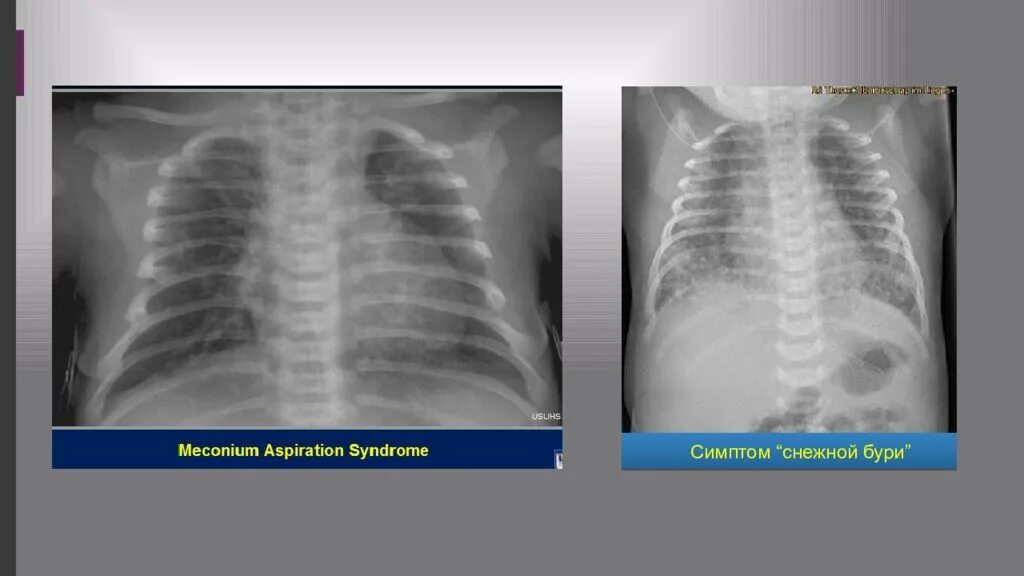

Синдром аспирации